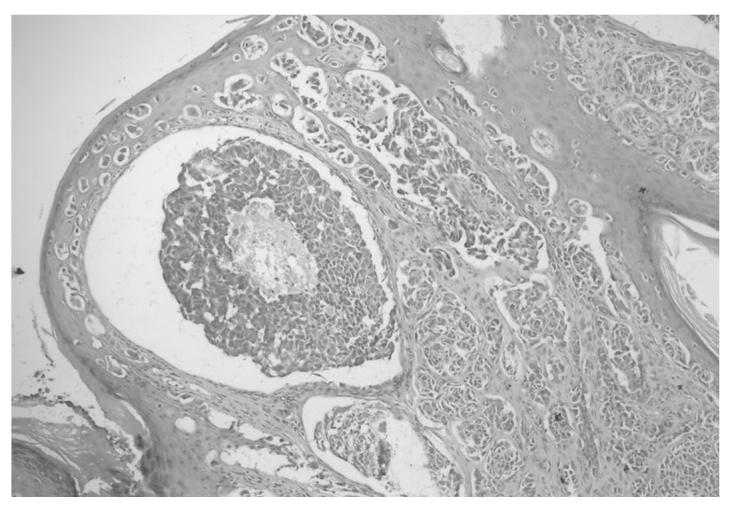

Malignant melanoma can be successfully treated when it is identified in its early stages, but the disease is associated with a poor prognosis when it is detected in an advanced stage. Papillary thyroid carcinoma is a thyroid cancer that has a good prognosis. The present study reports a rare case of malignant melanoma and papillary thyroid carcinoma that were diagnosed concurrently and treated simultaneously. The present patient was a 37-year-old male, in whom examination of a skin biopsy that was obtained from a lesion in the right retroauricular region revealed the lesion to be consistent with malignant melanoma. The patient underwent radical neck dissection upon the detection of malignant melanoma metastasis to the sentinel lymph node. Metastases of papillary thyroid carcinoma were detected in four out of 38 lymph nodes. The patient was then diagnosed with papillary thyroid carcinoma and underwent total thyroidectomy. The patient was administered with high-dose followed by moderate-dose interferon-α therapy for the treatment of malignant melanoma. The patient also received concurrent radioactive iodine therapy for the treatment of papillary thyroid carcinoma, at the same time as the interferon therapy. The two primary tumors of the patient were treated successfully. During therapy, no serious side-effects were observed, with the exception of fever caused by high-dose interferon therapy. Malignant melanoma and papillary thyroid carcinoma may occur concurrently, although this is rarely observed. The present study reports a rare case that demonstrates that the two tumors can be successfully treated simultaneously.